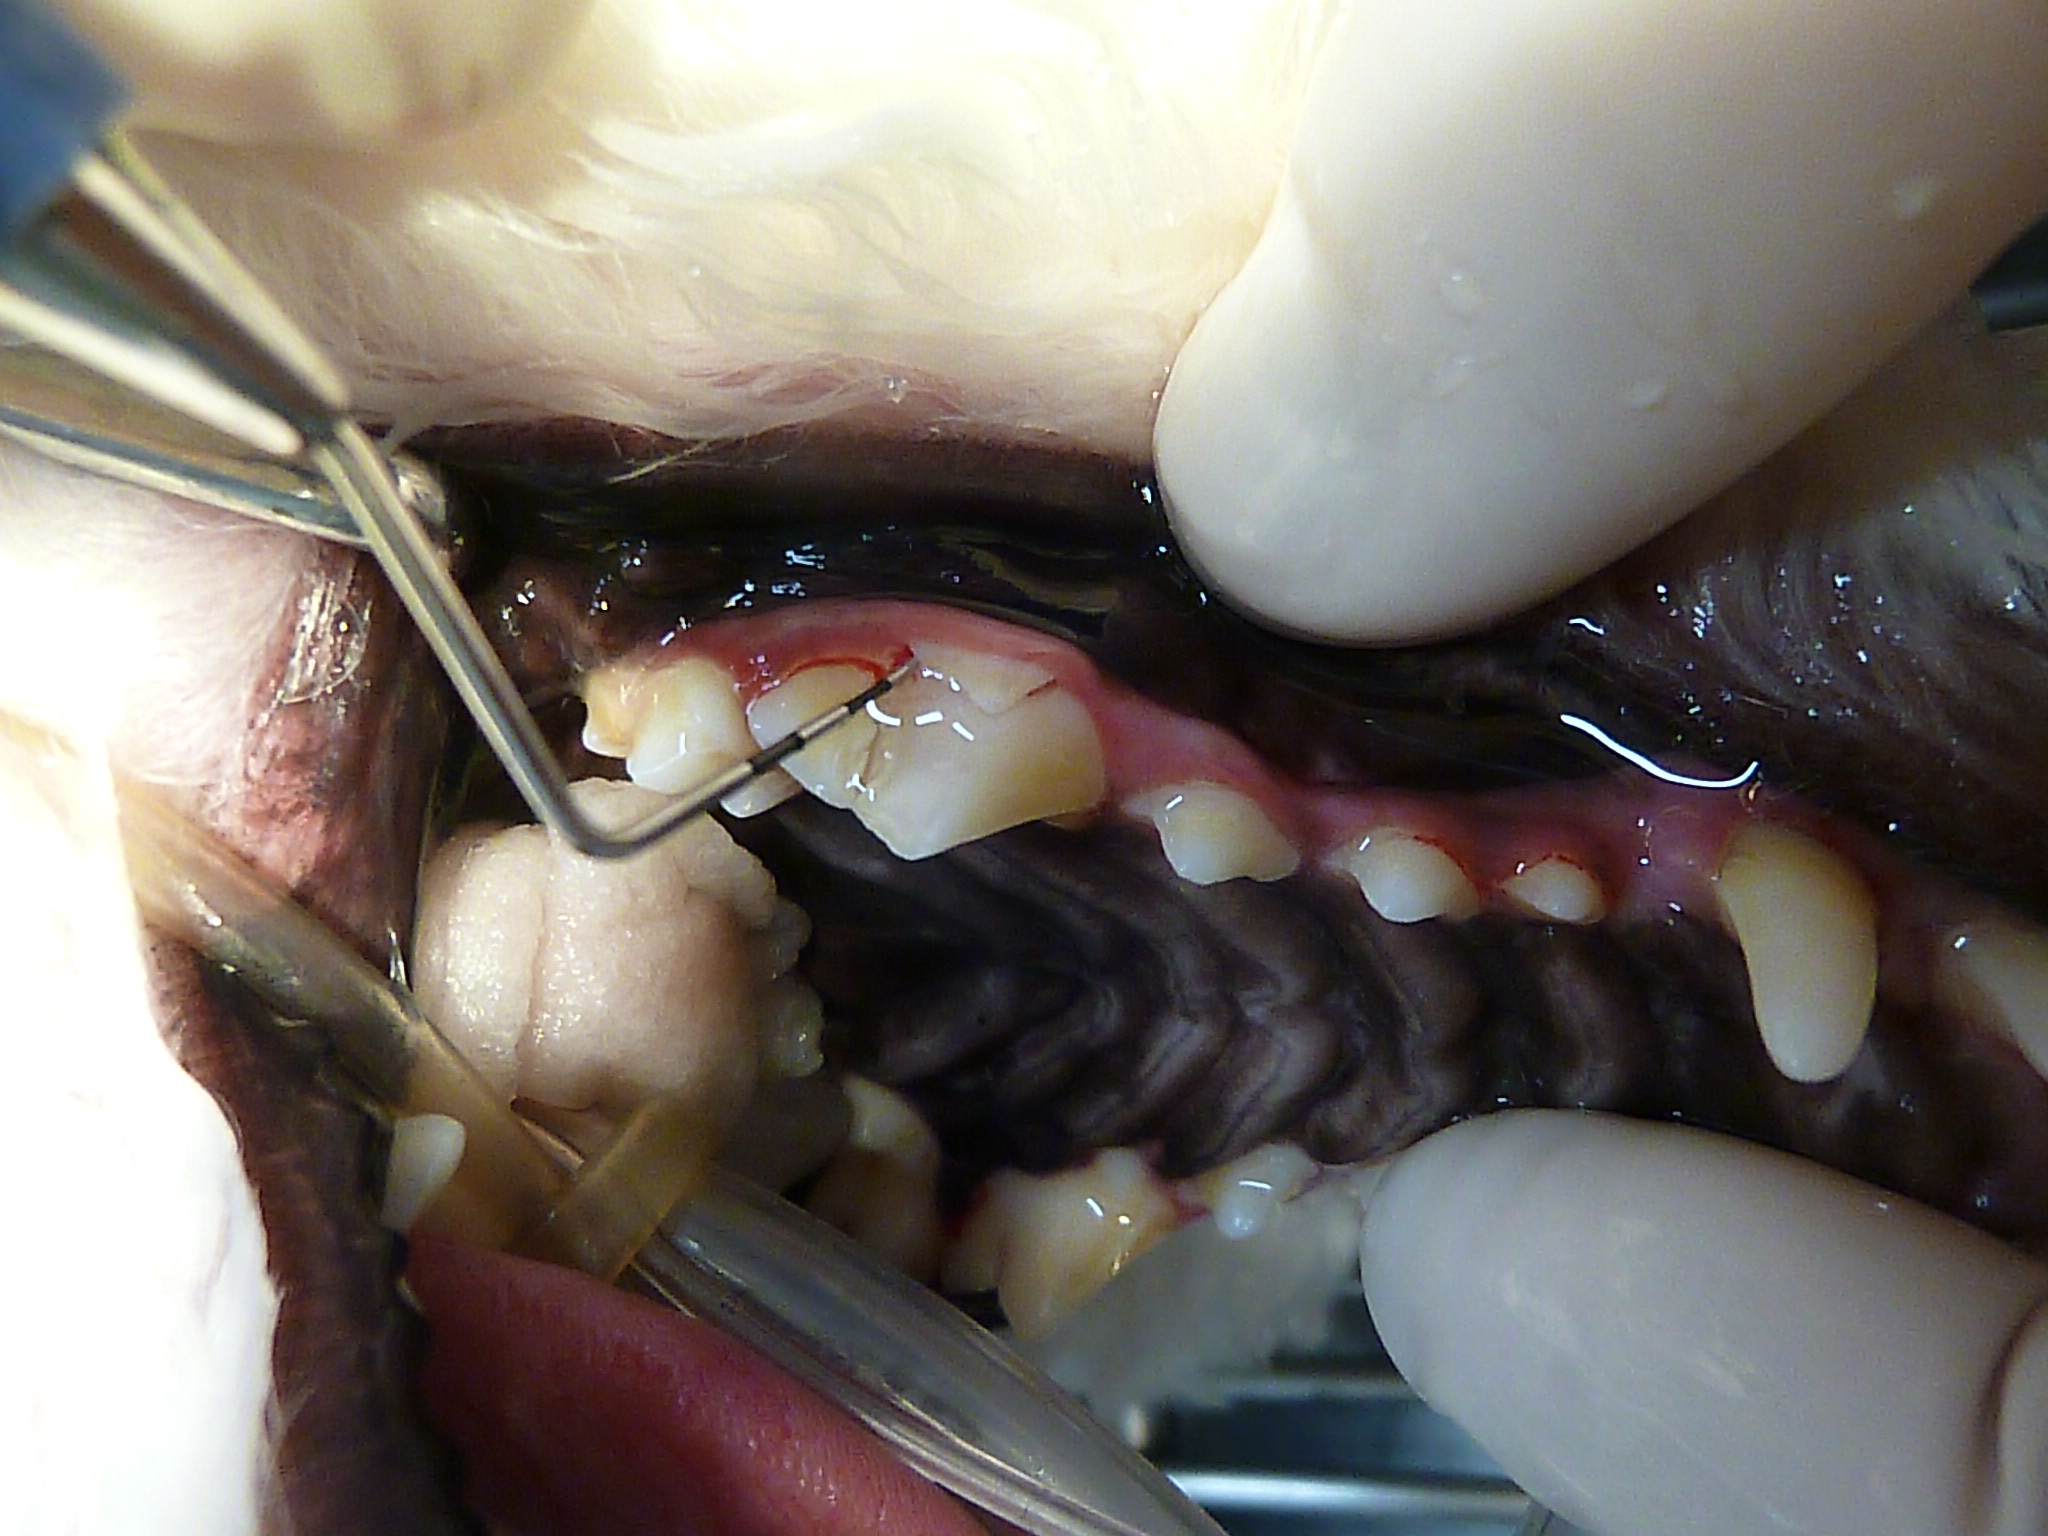

破折している右上顎第4前臼歯です。

歯面の歯石を取り除くと、

欠けた歯の一部が歯肉に付着した状態であることがわかります。